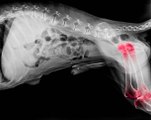

En cas de déshydratation ou de coup de chaleur, les conséquences peuvent être désastreuses... Mais comment reconnaître un coup de chaleur ?

1. Votre animal change d’attitude.

2. Sa température est anormalement élevée.

3. Il adopte une respiration irrégulière.

4. Il est pris de tremblements, de vomissements ou de vertiges.